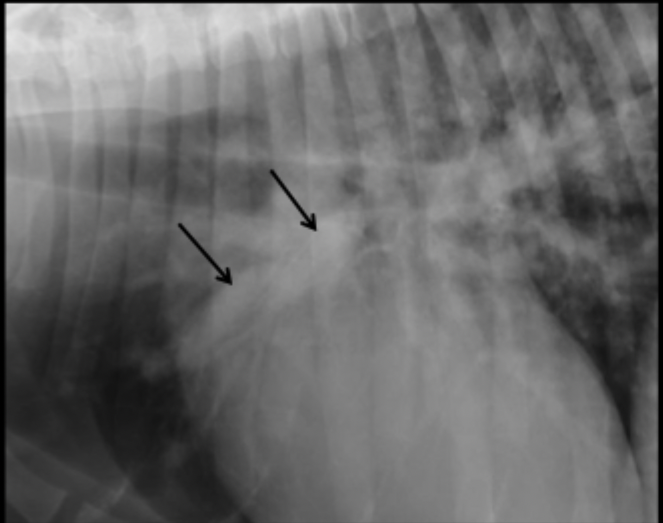

What can be seen in this magnified canine radiograph?

dilated cranial lobar artery due to heartworm disease